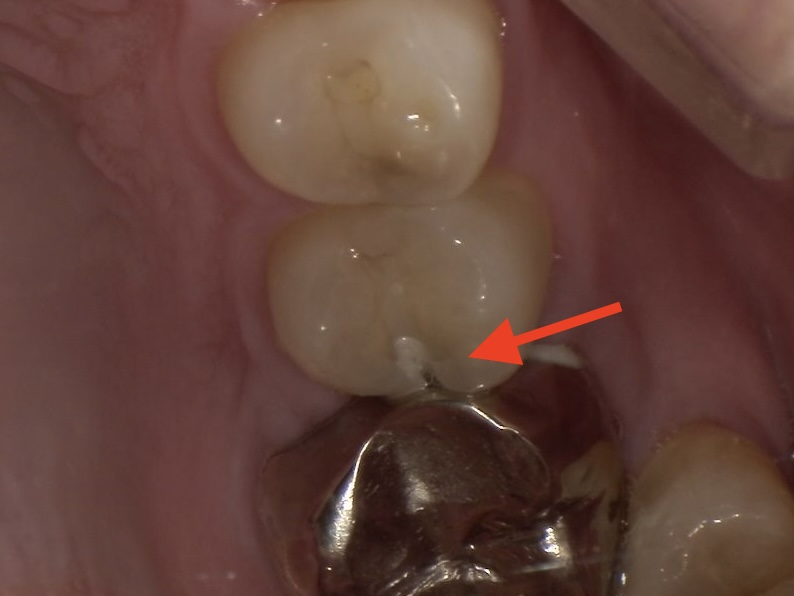

治療開始前です。

隣の銀歯との間からむし歯が進行しているようで、

表面には大きな穴はあいていません。

表面のエナメル質を削りました。

内部の柔らかくなっている部分が見えてきます。